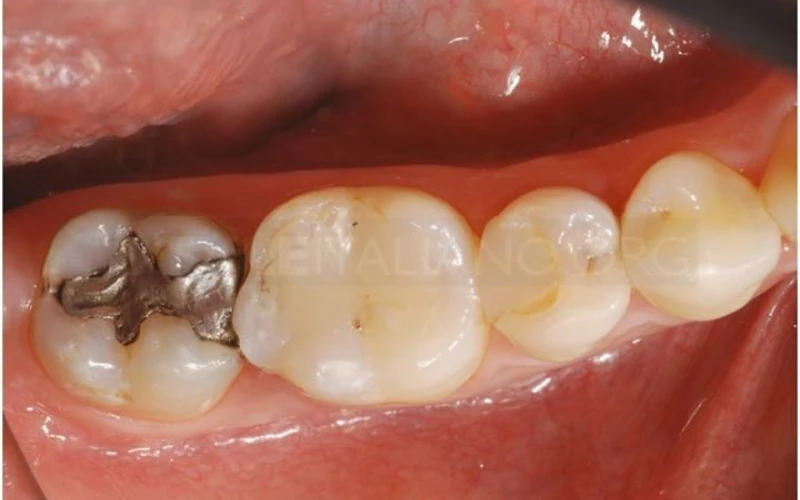

1. Khám ban đầu: Bệnh nhân phàn nàn về cơn đau xảy ra ở nhiều răng trên cùng một bán cung hàm.

3. Dung dịch phát hiện sâu răng hỗ trợ loại bỏ các mô bệnh.

4. Xoang hàn đã được làm sạch. Đây là thời điểm tốt nhất để lựa chọn kế hoạch điều trị.